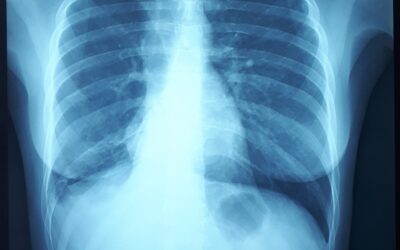

Клапанная бронхоблокация; Кровотечение из туберкулезных каверн легкого Больной 57 летний мужчина. В 2013 году был лечен по поводу туберкулеза легких. Несколько месяцев назад у него появилось кровохарканье с эпизодами кровотечения. Пациент постоянно находится на...